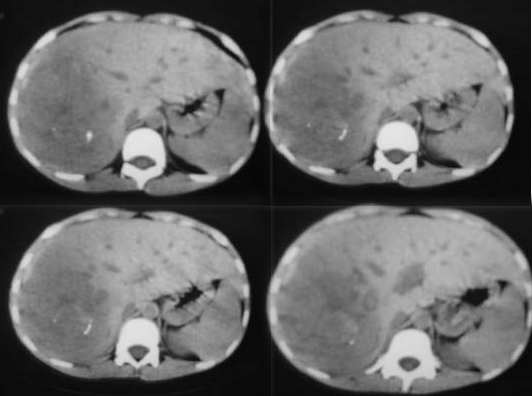

患者男性,10岁,腹痛4小时余,5年前患乙肝.查:右上腹压痛(+),反跳痛(+)血常规:wbs13.5x10(9)/l,b超提示:右肝实质性占位,性质待查.afp弱阳性患者男性,10岁,腹痛4小时余,5年前患乙肝.查:右上腹压痛(+),反跳痛(+)血常规:wbs13.5x10(9)/l,b超提示:右肝实质性占位,性质待查.afp弱阳性.

肝右叶巨大类圆形混杂密度影,边缘清晰,病变内部密度不均匀,可见环形钙化,我们考虑肝脏恶性肿瘤,肝母细胞瘤或肝细胞癌.请大家就平扫给予分析和指教.谢谢!!患者直接上省级医院检查,未做增强!

肝右叶见团块状混杂密度影,体积较大,密度不均匀,其内见低密度坏死区,并见点状、条状高密度钙化影,患者10岁,上腹痛,afp弱阳性,5年前患乙肝,首先考虑肝细胞癌,纤维板层样肝细胞癌不除外。增强扫描可鉴别,纤维板层样肝细胞癌,临床无特异性,以腹块和上腹部不适为主,无病毒性肝炎病史,实验室检查hbsag 阴性afp正常或略升高,ct表现病灶内出现钙化为其特点。

肝右叶巨大类圆形混杂密度影,边缘清晰,病变内部密度不均匀,可见环形钙化,结合临床考虑肝母细胞瘤可能性大。